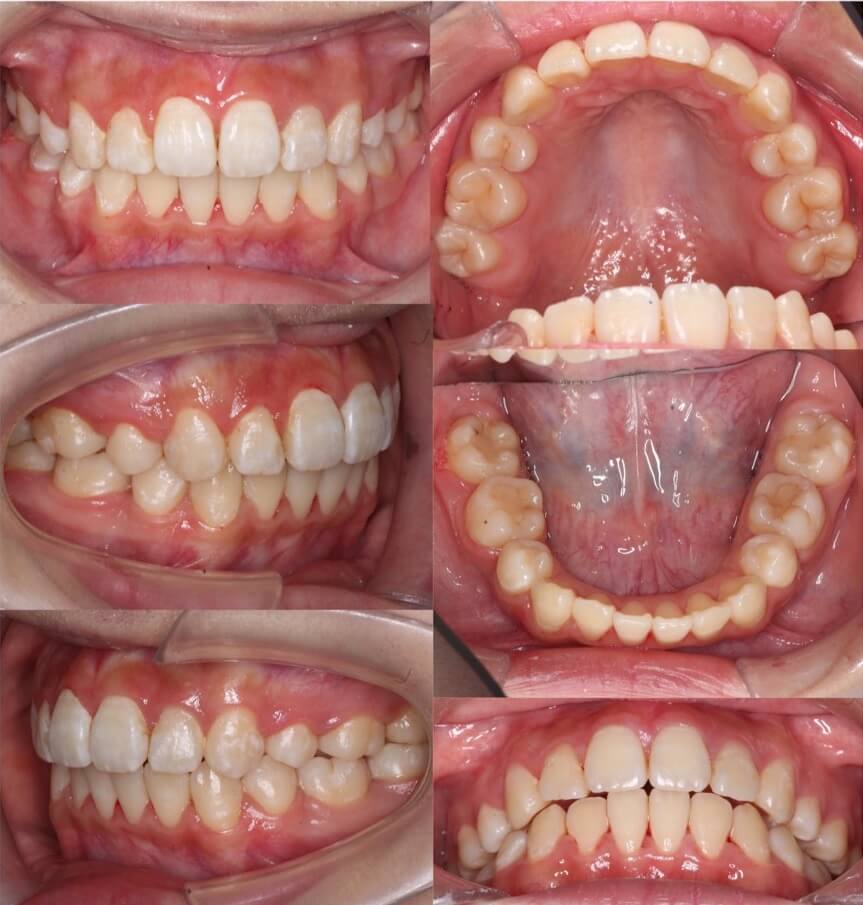

「ガミースマイルも改善」

20代女性・唇側矯正・上あご突出型

ガミースマイルをともなう口ゴボケースです。上の前歯の歯茎ににアンカースクリューを使用し、確実に圧下移動を行いました。「上あご前突型」は抜歯矯正でガミースマイルの改善もしやすいと言えます。

<症例概要> 難易度:★★★★★

主訴:口元の突出とガミースマイル

年齢・性別:10代女性

住まい:千葉県八千代市

症状:上顎前突・上下顎前歯唇側傾斜・ガミースマイル

治療方針:抜歯空隙の閉鎖(中等度固定)

治療装置:唇側矯正装置

固定:ナンスホールディングアーチ・前歯部歯科矯正用アンカースクリュー(計2本)

抜歯:上下左右4番(計4本)

治療期間:2年2か月

リテーナー:上下プレートタイプ+下フィックスタイプ

治療費用:990,000(税込)

代表的副作用:痛み・治療後の後戻り・歯根吸収・歯髄壊死・歯肉退縮